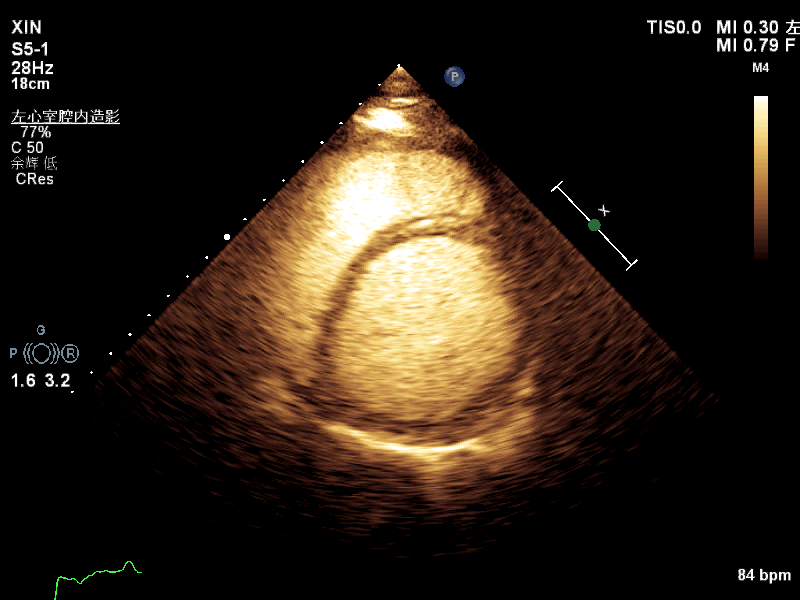

【特色診療】超聲心動圖及左心聲學(xué)造影評估化療藥物相關心髒毒性

鄭曉偉 林長(cháng)裕 普甯現代醫院